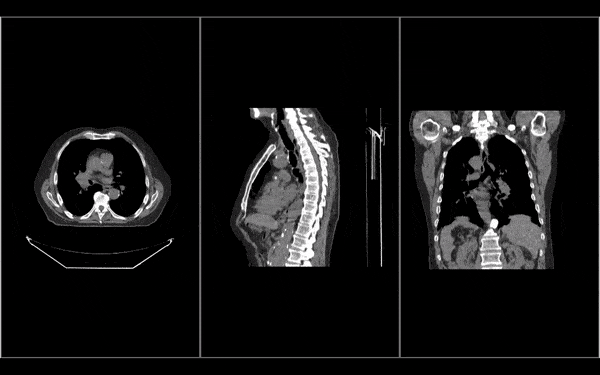

• Fuse and overlay multiple images such as PET/CT fusion